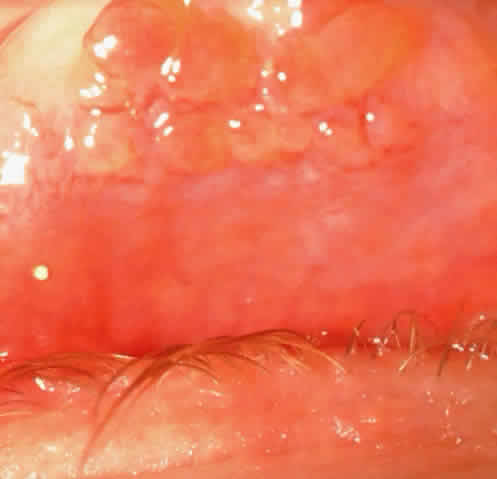

Patients with VKC may be divided into two groups based on clinical presentation: palpebral vernal and limbal vernal. Palpebral vernal involves the upper tarsal conjunctiva and is characterized by cobblestone papillae (i.e., papillae that have enlarged, often having flattened tops (Fig. 1). Papillae can be distinguished from follicles by their red centers; these centers consist of the dilated blood vessel at the core of the papilla surrounded by inflammatory cells. A sequela that may occur in VKC is conjunctival scarring that has a lacy appearance at the base of the old papillae. Although rare, there may be lacy scarring that extends superiorly into the fornix (Fig. 2). On rare occasions there may be conjunctival cysts (Fig. 3) and enough scarring to cause symblepharon formation. Fibrin that is enhanced by heat may accumulate on the giant papillae and is known as the Maxwell-Lyons sign.4

Fig. 1. Clinical photograph of the upper palpebral conjunctiva showing cobblestone papillae with their flat-top appearance.